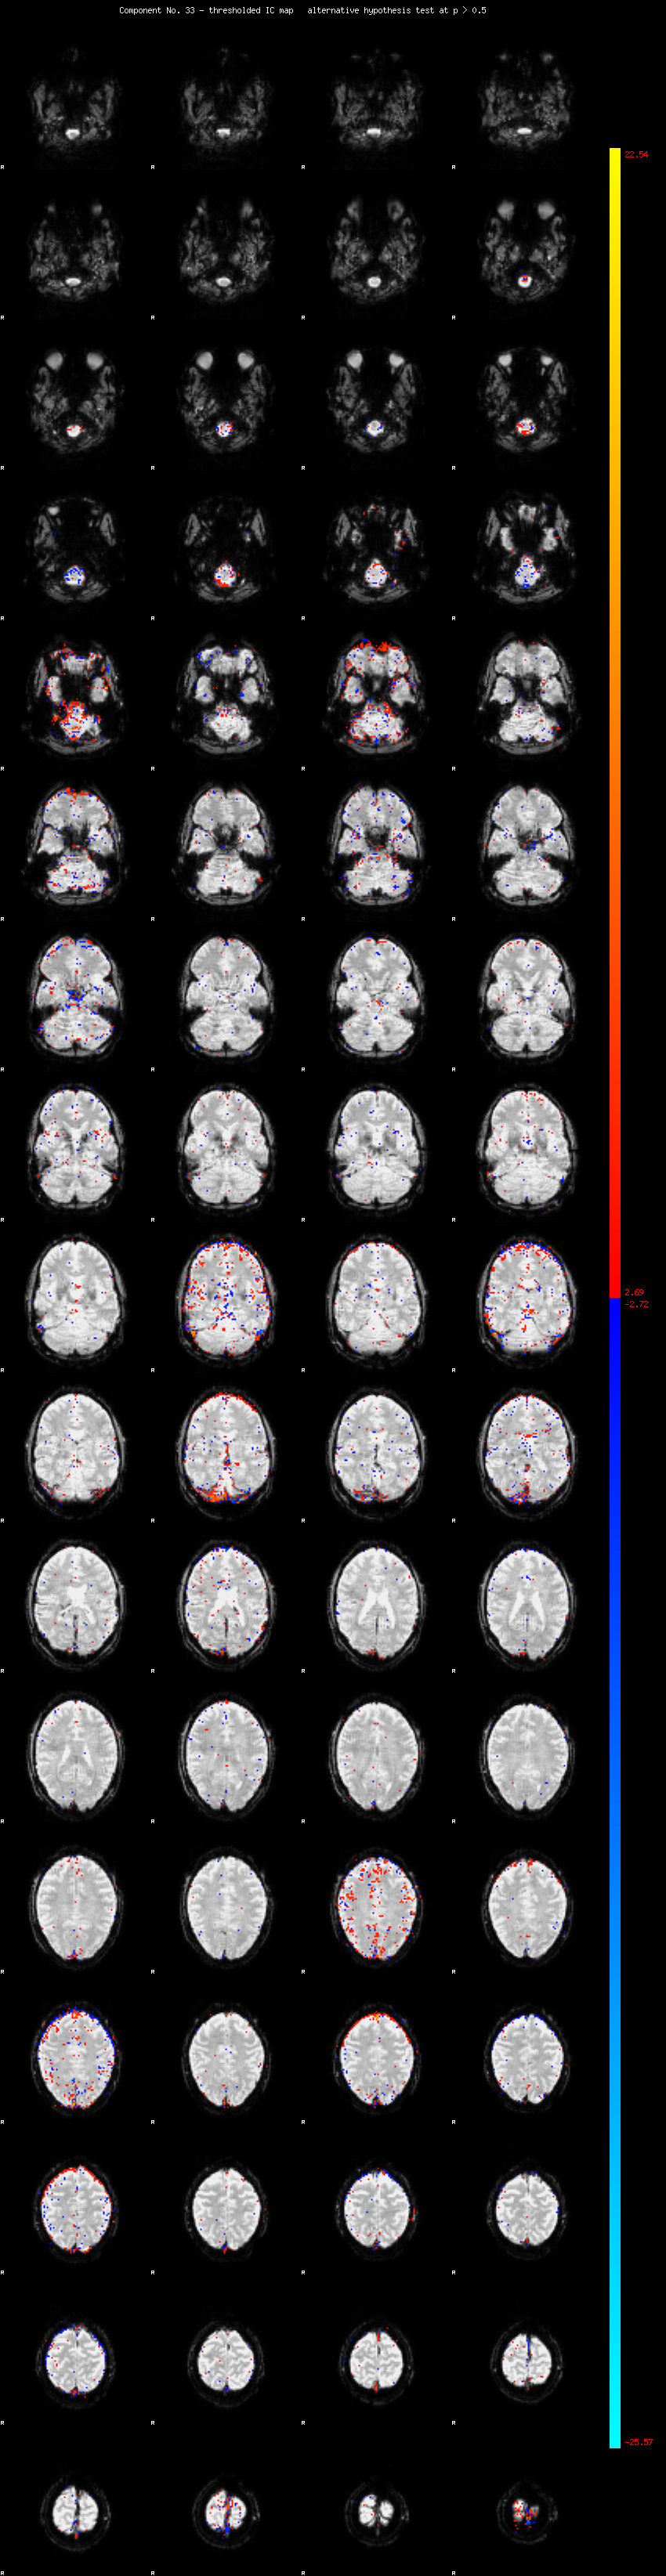

MELODIC Component 33

1.19 % of explained variance;     0.79 % of total variance